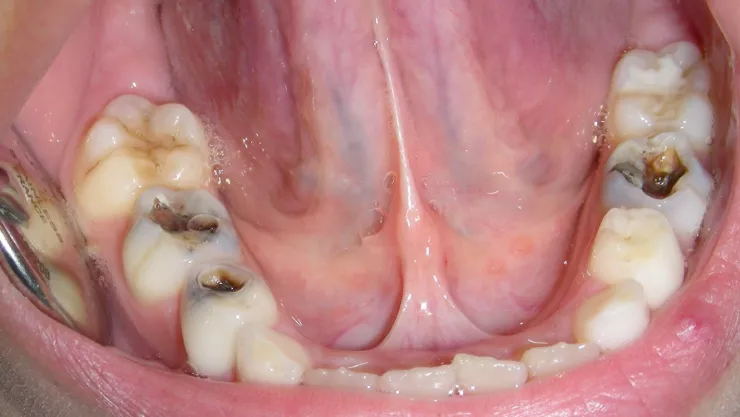

En México hay cerca de 10 millones de niños con caries

Este padecimiento provoca futuros problemas dentales, señaló una experta.

En México, aproximadamente 10 millones de niños entre los dos y cinco años padecen caries, lo que representa un grave problema de salud bucal desde edades tempranas, de acuerdo con la Dirección General de Epidemiología de la Secretaría de Salud.

La caries en la infancia temprana, antes conocida como caries de biberón, se presenta en los bebés debido a la falta de higiene bucal después de ser alimentados con leche materna o fórmulas.

Este padecimiento provoca futuros problemas dentales, además de afectar el crecimiento, interferir con la alimentación, el sueño y la concentración en la escuela, explicó María Gloria Hirose López, profesora de la Facultad de Odontología (FO) de la UNAM.

“La caries es una enfermedad crónica que avanzan rápidamente, y es irreversibles si no se atiende a tiempo. En los niños, se presenta principalmente en los dientes superiores anteriores y en los molares, porque la lengua cubre los dientes inferiores cuando se toma el biberón o son amamantados. Por ello, la limpieza bucal debe hacerse inmediatamente después de alimentar al bebé”, subrayó la académica.

Los dientes primarios son la guía para la erupción de los permanentes, y de no ser atendidos, estos últimos saldrán afectados.